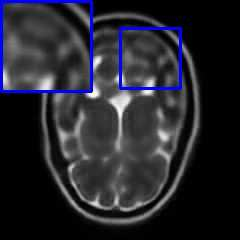

Limited by imaging systems, the reconstruction of Magnetic Resonance Imaging (MRI) images from partial measurement is essential to medical imaging research. Benefiting from the diverse and complementary information of multi-contrast MR images in different imaging modalities, multi-contrast Super-Resolution (SR) reconstruction is promising to yield SR images with higher quality. In the medical scenario, to fully visualize the lesion, radiologists are accustomed to zooming the MR images at arbitrary scales rather than using a fixed scale, as used by most MRI SR methods. In addition, existing multi-contrast MRI SR methods often require a fixed resolution for the reference image, which makes acquiring reference images difficult and imposes limitations on arbitrary scale SR tasks. To address these issues, we proposed an implicit neural representations based dual-arbitrary multi-contrast MRI super-resolution method, called Dual-ArbNet. First, we decouple the resolution of the target and reference images by a feature encoder, enabling the network to input target and reference images at arbitrary scales. Then, an implicit fusion decoder fuses the multi-contrast features and uses an Implicit Decoding Function~(IDF) to obtain the final MRI SR results. Furthermore, we introduce a curriculum learning strategy to train our network, which improves the generalization and performance of our Dual-ArbNet. Extensive experiments in two public MRI datasets demonstrate that our method outperforms state-of-the-art approaches under different scale factors and has great potential in clinical practice.